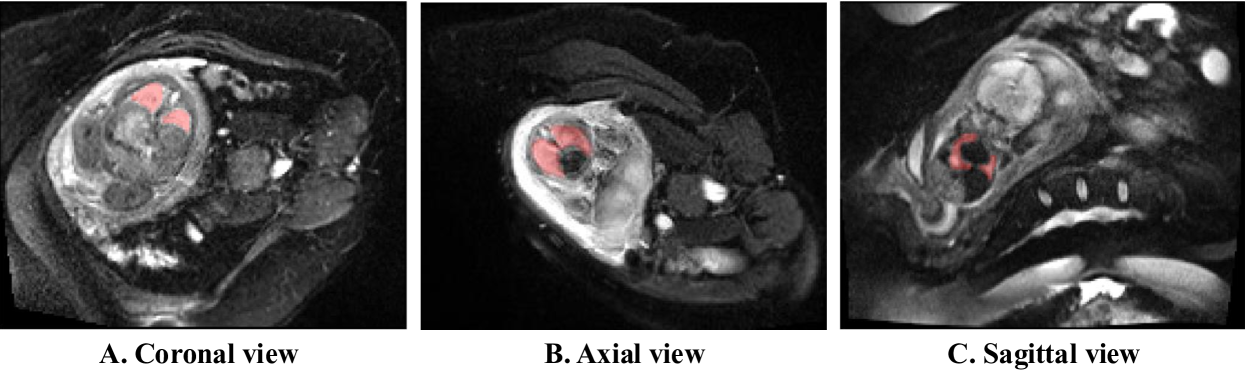

We collected a total of 95 fetal 4D DWI MRI scans from 30 pregnant women (16 FGR pregnancies, 14 controls/normal pregnancies) at University College Hospital, London. The imaging orientation is defined relative to maternal anatomy (see Fig. 2) and there are 20 axial cases and 10 coronal cases in the dataset. The gestational age (GA) ranged from 20+0 to 36+0 weeks, with a median GA of 28+2 weeks overall (FGR: 28+2; control: 28+0). All scans were acquired using a 1.5T MRI system (Siemens Healthineers, Erlangen, Germany) with a spin-echo echo-planar imaging (SE-EPI) sequence. The protocol included multiple b-values (0–600 s/mm²) and diffusion directions to capture IVIM dynamics. Each 4D scan typically contained 7–10 temporal frames, each representing a 3D volume.

Refer to caption

Figure 2: Representative fetal lung visibility in different views. (A) Coronal and (B) axial views show clear lung boundaries, while (C) sagittal view has poor definition, limiting its segmentation utility.